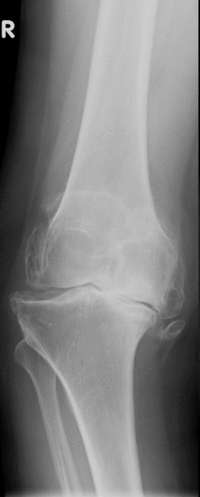

Diagnostik

Neben einer klinischen Untersuchung steht die Röntgenuntersuchung an erster Stelle zur Diagnosestellung. Weitere Untersuchungsmethoden wie MRT und CT-Aufnahmen sind hierbei von untergeordneter Bedeutung.